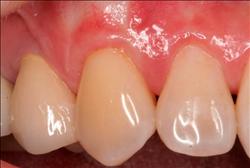

Cosmetic Soft Tissue Grafting

In addition to the functional problems previously mentioned, receding gums can look unsightly.

Longer looking teeth and exposed tooth roots give an "old" appearance to your smile. Some people cover their mouths when they smile for this very reason.

Cosmetic Soft Tissue Grafting can add a new youthful appearance to your smile. In your initial consultation with Dr. Hoidal, he will thoroughly explain what can be achieved in your particular case.